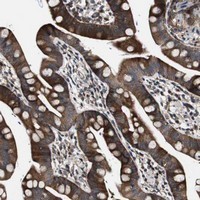

- Immunohistochemical staining of human small intestine with GALNT8 polyclonal antibody (Cat # PAB20609) shows strong cytoplasmic positivity in glandular cells at 1:50-1:200 dilution.

- Immunohistochemistry (Formalin/PFA-fixed paraffin-embedded sections)